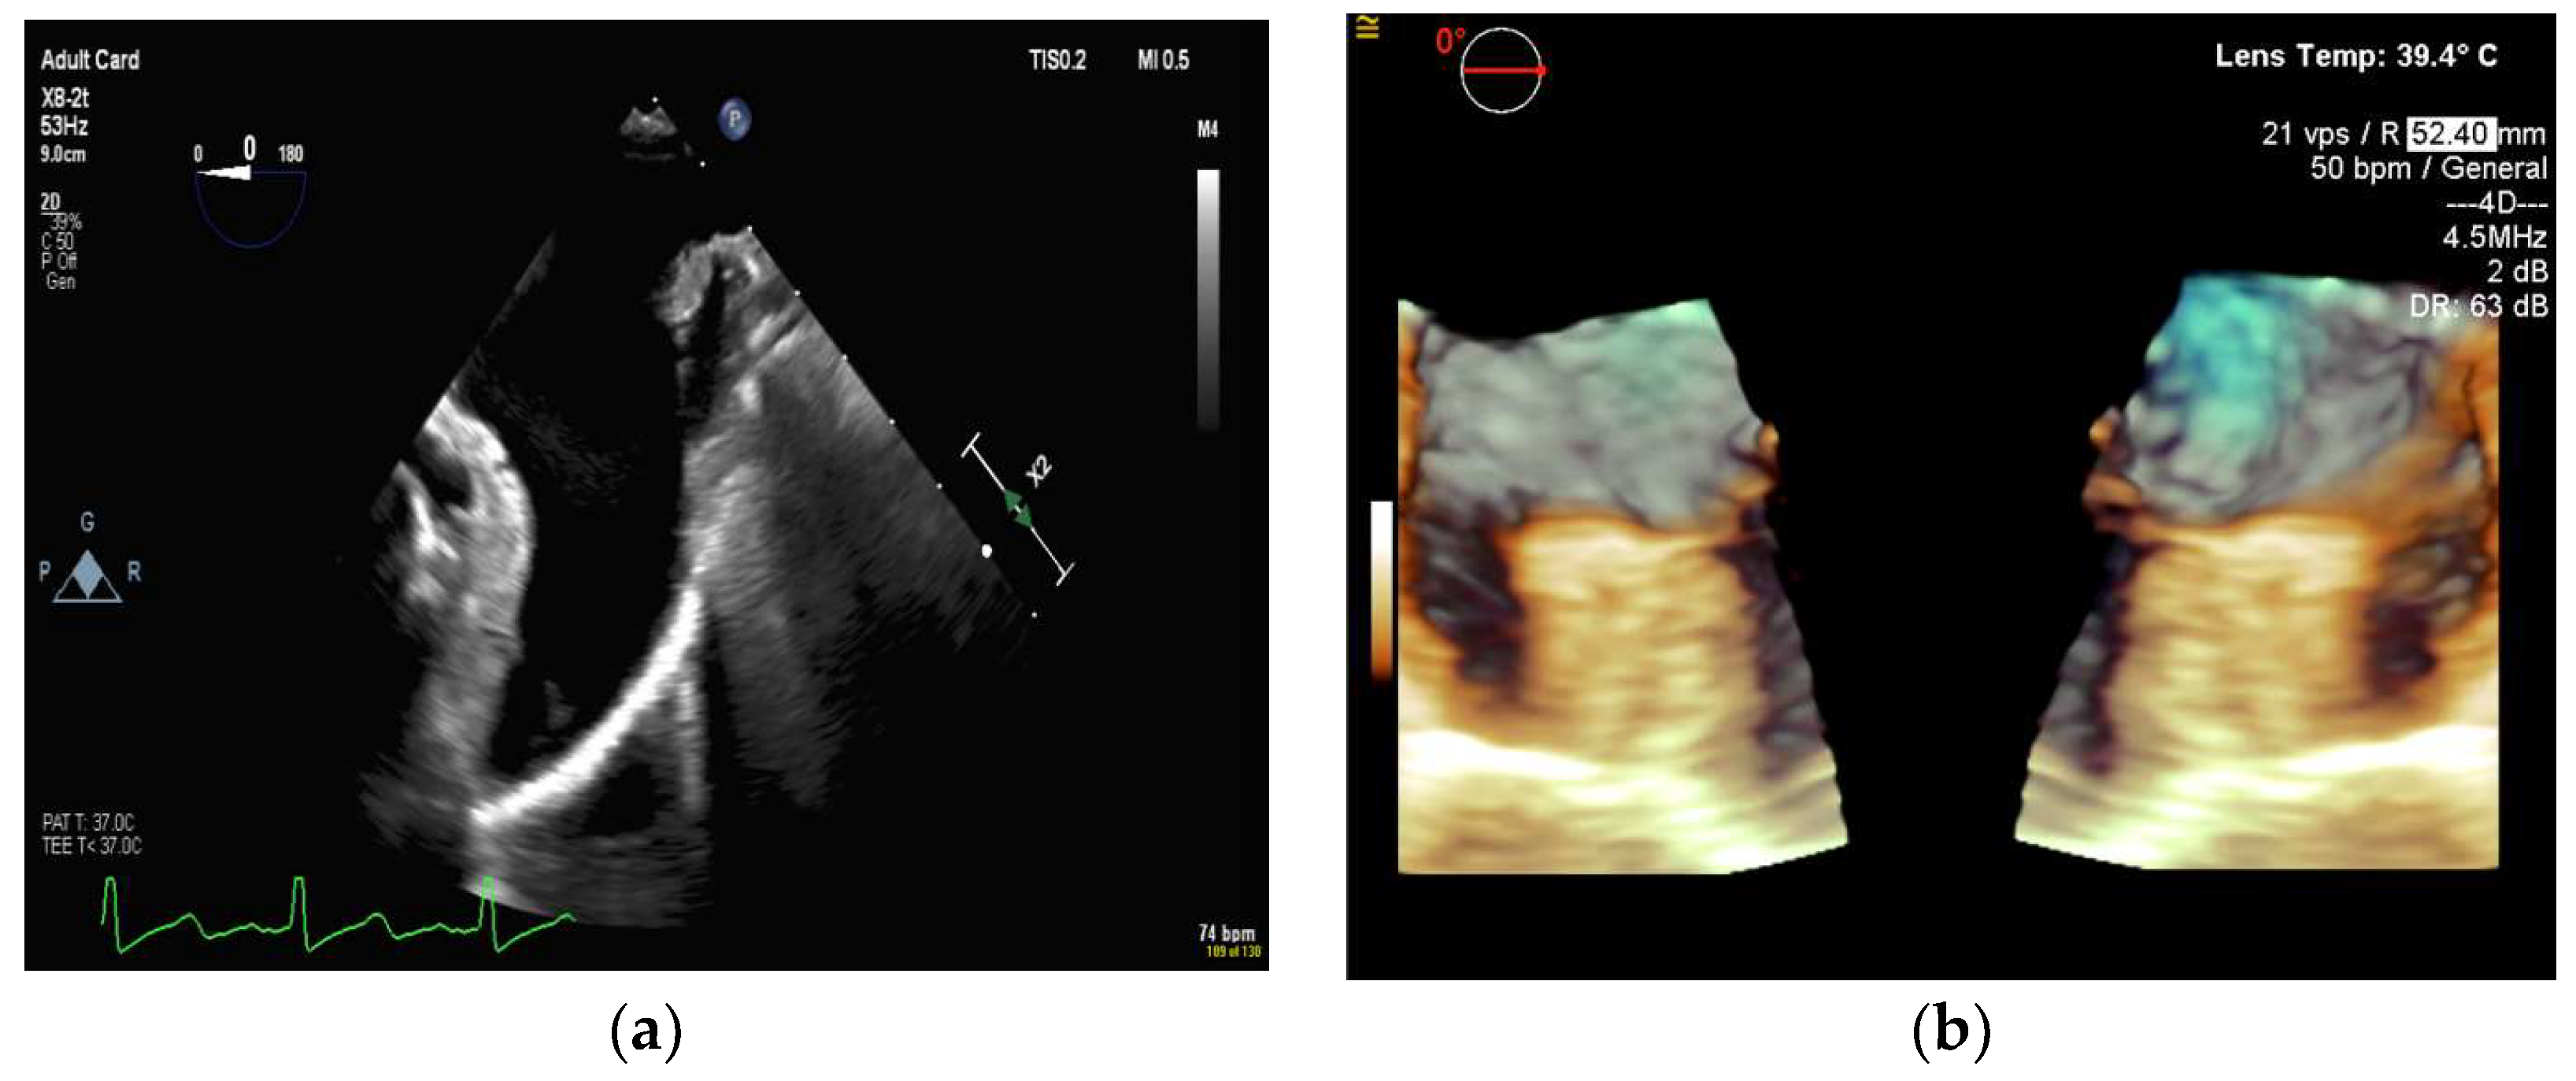

4.2.3. Mitral Valve Repair